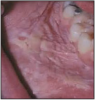

Figure 8 – Verrucous carcinoma. Image provided by: Dr. JE Bouquot

Figure 8

Verrucous carcinoma is a warty variant of squamous cell carcinoma characterized by a predominantly outward overgrowth of well-differentiated keratinized epithelium.30 Intraoral lesions appear keratinized with white finger-like projections.